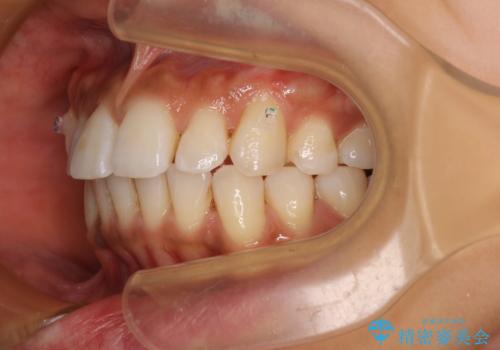

カリエール・ディスタライザーを併用したインビザライン矯正治療

カリエールディスタライザーを併用したことで、確実かつ短期間で治療を終えることができました。

- 全体的な歯列の叢生を気にして来院された患者様です。

奥歯の咬み合わせを見ると、片方は上顎が下顎に対して相対的に前方にある状態でした。

咬み合わせを改善するためには、上顎臼歯を後方に移動させた咬み合わせにする必要があります。

インビザライン単体で改善することも可能ですが、ディープバイトのためインビザライン単体で達成する可能性が低いと考えられたため、カリエール・ディスタライザーという補助装置を併用して、より確実性を上げることとしました。

奥歯の咬み合わせ改善後に、インビザラインにて歯列を整えることとしました。